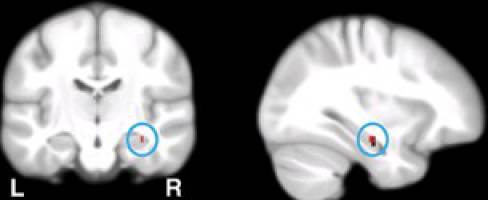

Gesundheit - Psychologie - 02.09.2015

Gene sind sowohl für die normale Gedächtnisleistung, als auch für die Entstehung der Alzheimer-Krankheit entscheidend. Wissenschaftler der Universität Basel haben nun nachgewiesen, dass eine bestimmte Gen-Gruppe an beiden Vorgängen zentral beteiligt ist. Es handelt sich dabei um Moleküle, welche die Konzentration der Kalzium-Ionen in Zellen steuern.

Gesundheit - 25.06.2015

Zielgruppeneinstiege Navigation Mitarbeitende weitere Informationen Alumni weitere Informationen Medien weitere Informationen Forschende weitere Informationen Dozierende weitere Informationen Doktorierende weitere Informationen Studieninteressierte weitere Informationen Studierende weitere Informationen Studierende aus dem Ausland weitere Informationen Fruchtzucker sättigt nicht nur weniger, sondern stimuliert auch das Belohnungssystem im Gehirn in geringerem Mass als Traubenzucker.